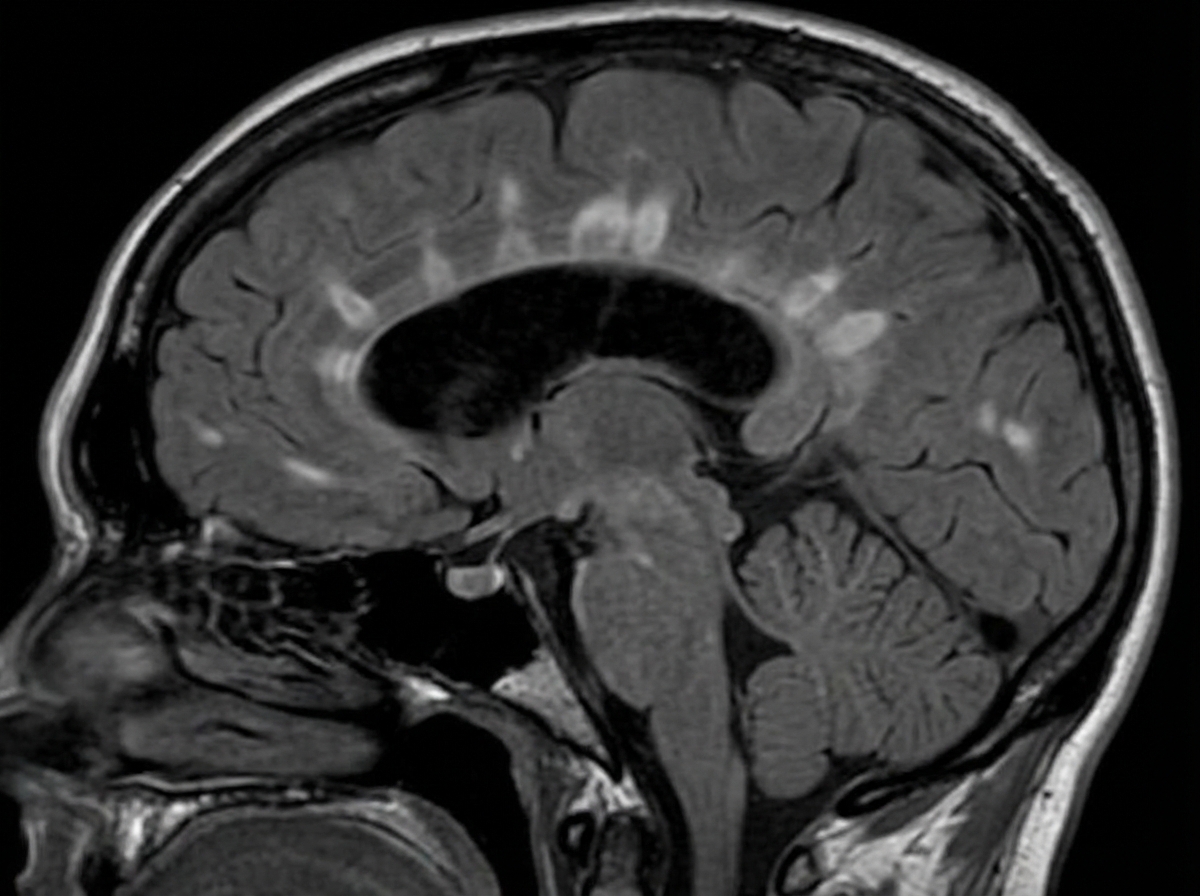

A 29-year-old woman presents with progressive vision loss in her right eye and periorbital pain for 5 days. She says that she has also noticed weakness, numbness, and tingling in her left leg. Her vital signs are within normal limits. Neurological examination shows gait imbalance, positive Babinski reflexes, bilateral spasticity, and exaggerated deep tendon reflexes in the lower extremities bilaterally. FLAIR MRI is obtained and is shown in the image. Which of the following is the most likely cause of this patient’s condition?